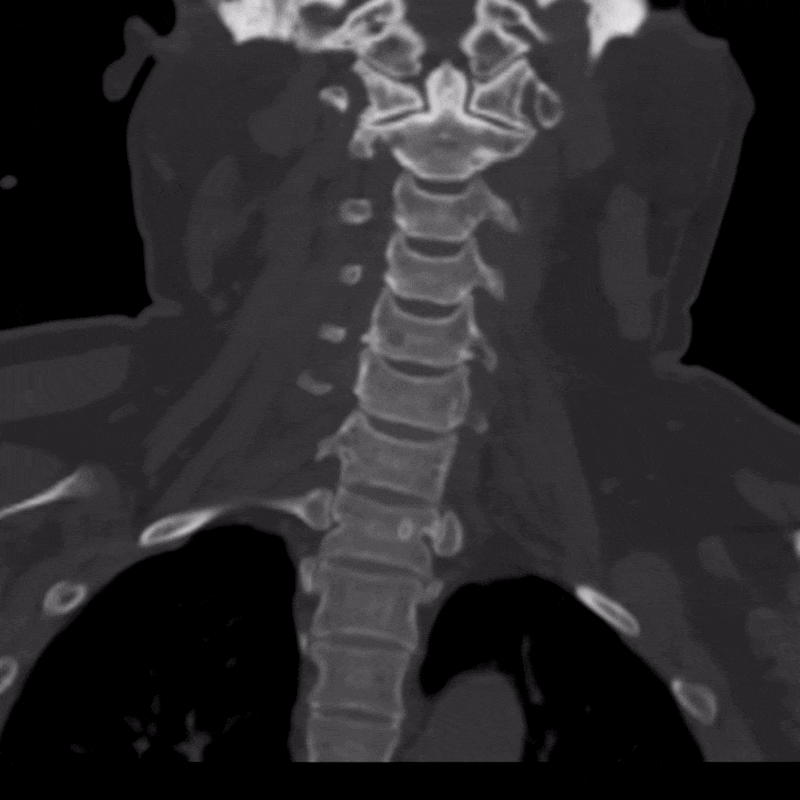

A CT scan of the cervical spine was obtained to further evaluate the presence and severity of OPLL. CT is well suited for this assessment because it clearly depicts bone and calcified structures, allowing the ossified ligament to be easily distinguished from surrounding soft tissues. The scan confirmed extensive OPLL from C2 through C6 with severe spinal canal stenosis.

Using the CT dataset, a radiologic technologist processed the images to create a series of advanced visualizations that highlight the distribution of ossification and its relationship to surrounding anatomy. These images provide different perspectives of the cervical spine and help translate cross-sectional findings into more intuitive views.

Figure C: 360-degree CPR view of the vertebral bodies.